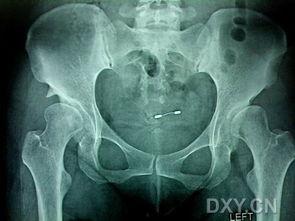

首先,得先弄清楚什么是成人髋脱位。简单来说,它就是髋关节脱位的一种,通常发生在老年人身上。由于关节周围的肌肉、韧带等组织随着年龄的增长而逐渐退化,导致关节稳定性下降,从而引发髋关节脱位。